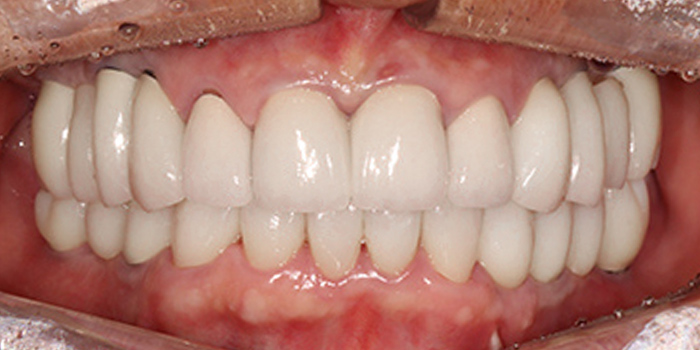

03 60대 만성치주염 남성, 앞니 심미적 개선, 저작 기능의 회복, 치료기간 7개월 -

04 60대 만성치주염 남성, 앞니 심미적 개선, 저작 기능의 회복, 치료기간 7개월 -